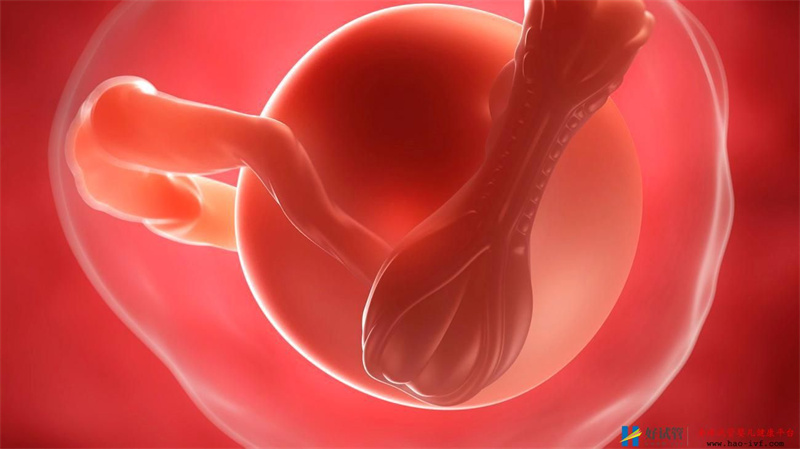

鲜胚是指取卵完后三天胚胎出结果,如果在这一天移植,就叫移植鲜胚,如果在这一天没有移植,而是把胚胎冻起来,以后再移植就叫做冻胚。 但是冻胚和鲜胚移植那个成功率更高一些呢?把胚胎冷冻起来会不会冻坏,或者胚胎活力降低,胚胎发育异常此类的问题发生?想必大家都有此疑问吧。 大多数人都感觉鲜胚更容易成功,因为它是刚取出的卵是新鲜的、更具有活力、更符合自然规律,想当然的就更容易成功;那么到底哪个成功率更高呢?

有临床表示鲜胚与冻胚成功率是一样的,也有研究表明冷冻胚胎移植成功率更高;其实从不同角度看,就有不一样的结果。 1.从胚胎的角度来说,鲜胚比较好,充满活力; 2.从母体来讲是冻胚好,但冻胚有可能造成胚胎质量下降; 另外补充一点,胚胎冷冻只是让细胞停止运动,并非中断,不会破坏胚胎的活力和规律,只要在给它恢复温度,就可以再生长。 前不久,冷冻了18年的胚胎被“唤醒”,并成功移植到妈妈的子宫内。经过十月怀胎,准妈妈顺利的产下一名女婴。这个女宝被称为中国最“抗冻”宝宝,她生产时重3300克,身体指标一切正常。 它的成功也成功的把胚胎冷冻技术带进了我们的视线,也因此宝妹才会谈冷冻胚胎这项技术。